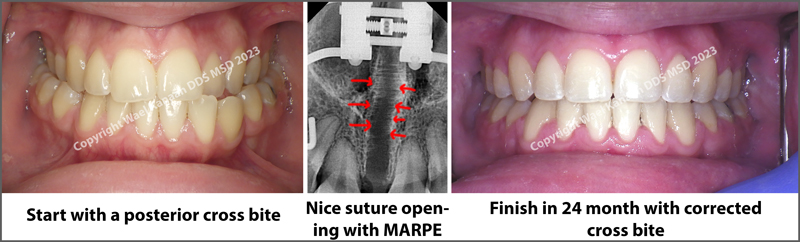

To make crooked teeth straight and correct crossbites, an expansion might be needed during orthodontic treatment to create enough space and accommodate the crooked teeth. This is usually carried with a traditional orthodontic expander called the Rapid Palatal Expander RPE.

However, in extremely narrow cases with a deficiency of more than 5 mm, "like Fig. 1” or in older patients, the traditional RPE might not work for the upper jaw, and a more aggressive approach might be needed to open the mid-palatal suture.

- Crossbite correction in adult non-growing patients

Case #6 with two-stage MSE and using only two screws

This patient was looking for an orthodontist in Houston who specialized in MSE expansion to improve her breathing while sleeping with her mouth open. She has a very narrow upper jaw, with the posterior teeth not visible while smiling.

Dr. Kanaan made her a custom-made MSE using only a 2-screw narrow MSE. Dr. Kanaan was not satisfied with the width after stage one and decided to do a second stage to get further expansion and enhance her breathing. The final results were magnificent, and the patient was extremely pleased with her functional, breathing, and cosmetic results.

Notice the above sequence of changes in her upper jaw width. The X-rays below also show her expansion and suture opening after stage one and after stage two.